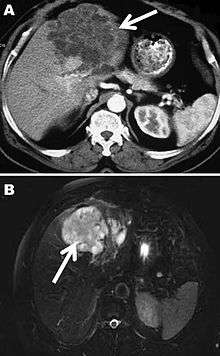

Computed tomography (A) and magnetic resonance (B) images of the liver of a 72-year-old man from French Guiana with polycystic echinococcosis affecting the left side of the liver. White arrows indicate the multicystic liver lesion.

A formal diagnose of any type of echinococcosis requires a combination of tools that involve imaging techniques, histopathology, or nucleic acid detection and serology. For cystic echinococcosis diagnosis, imaging is the main method—while serology tests (such as indirect hemogglutination, ELISA (enzyme linked immunosorbent assay), immunoblots or latex agglutination) that use antigens specific for E. granulosus verify the imaging results. The imaging technique of choice for cystic echinococcosis is ultrasonography, since it is not only able to visualize the cysts in the body's organs,[17] but it is also inexpensive, non-invasive and gives instant results.[18] In addition to ultrasonography, both MRI and CT scans can and are often used although an MRI is often preferred to CT scans when diagnosing cystic echinococcosis since it gives better visualization of liquid areas within the tissue.[17]

Similar to the diagnosis of alveolar echinococcosis and cystic echinococcosis, the diagnosis of polycystic echinococcosis uses imaging techniques, in particular ultrasonography and CT scans, to detect polycystic structures within the patient’s body. However, imaging is not the preferred method of diagnosis since the method that is currently considered the standard is the isolation of protoscoleces during surgery or after the patient’s death and the identification of definitive features of E. oligarthrus and E. vogeli in these isolated protoscoleces. This is the main way that PE is diagnosed, but some current studies show that PCR may identify E. oligarthrus and E. vogeli in patients’ tissues.[19] The only drawback of using PCR to diagnose polycystic echinococcosis is that there aren’t many genetic sequences that can be used for PCR that are specific only E. oligarthrus or E. vogeli.[10]